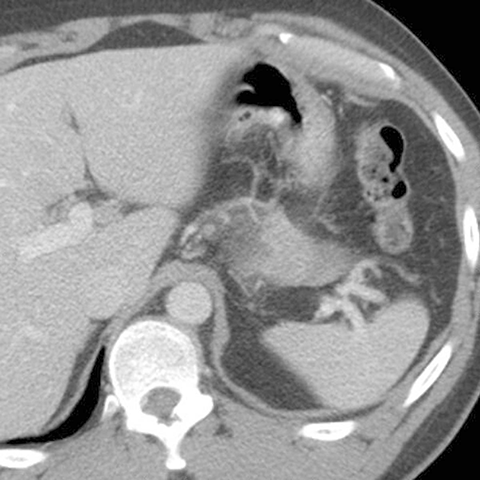

Normal spleen, axial view (CT) [3 of 5]